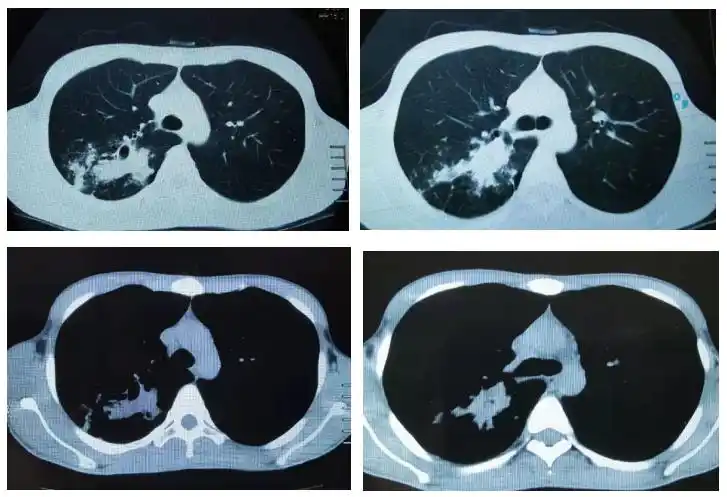

多发小结节状卫星灶的肺结核